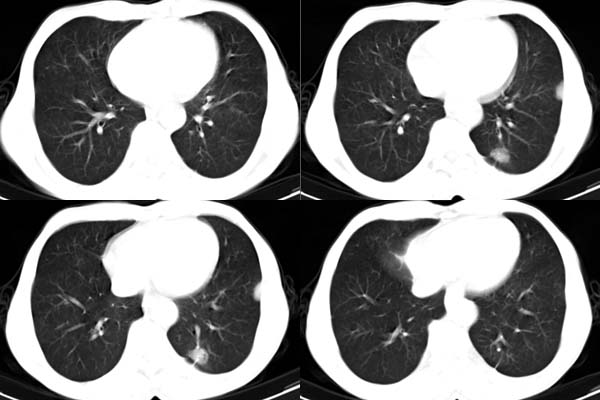

患者,男,65岁,咳嗽,胸痛

ct所见;左下肺可见片状阴影,密度不均,边缘尚清晰,胸膜方向见有条索相连,纵隔窗未见具体结节。左侧胸膜下见多个软组织结节且以宽基底与胸膜相连,右侧胸锁关节层面亦见软组织结节广基与胸膜相连。纵隔未见肿大淋巴结,气管,支气管开口正常。

左肺下叶基底段见结节样稍高密度影,内密度不均匀,边缘不清,可见索条影与邻近胸膜粘连,左侧胸膜上见多个结节影,以宽基底与胸膜粘连.纵隔不宽,内未见明确肿大的淋巴结.

ct所见:左肺上、下叶近胸膜肺外带可见多个大小不等的结节灶,边界清楚,边缘比较光整。近胸膜病灶似与胸膜以宽基底紧连。提供的病史比较简单,我考虑:1、胸膜原发肿瘤可能性大(就形态来看恶性可能性不大);那么大胆的设想一下,左下叶结节是否与它有必然的联系呢?也可以是结核或周围型肺癌。2、还可以考虑为胸膜和肺内的都是转移灶,病人65岁,是不是其他部位的恶性肿瘤转移过来的呢?因为病灶比较表浅,但一侧发病较少见。3、周围型肺癌并胸膜转移的可能性比较小,一是肺内病灶较小,单发,胸膜结节相对较多,位置较远,临近胸膜无受侵。